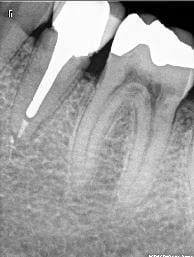

Une autre radio, après dépose...

A l'apex vous ne voyez pas comme l'apex avec fracture horizontal ? en meme temps je l'ai trop regardé cette radio, elle m'aveugle !

D'un autre coté, vu la taille du pivot, c'est un miracle s'il n'y a pas fracture.

Moi ce que çà m'évoque c'est une possible perforation de la racine par le tenon dans le sens vestibulo-lingual. Vu la longueur du tenon c'est possible. Le tenon a-t-il un axe bizarre ? Un saignement dans le canal c'est pas bon signe.